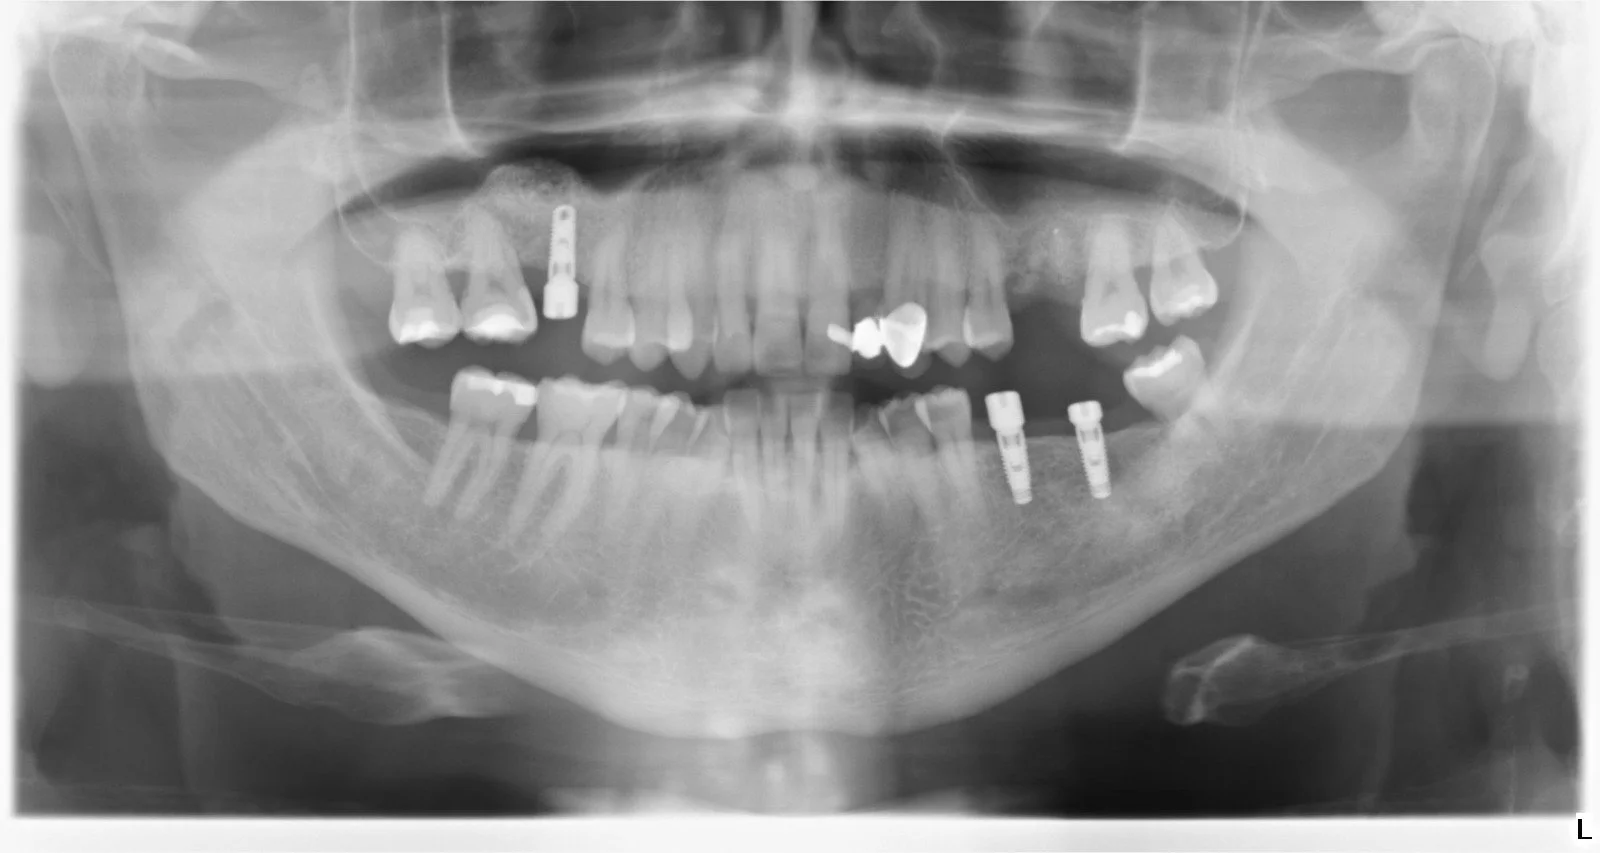

Después de un examen clínico y radiológico con CBCT en 3D, el cirujano le puede indicar si usted es candidato a este tratamiento.